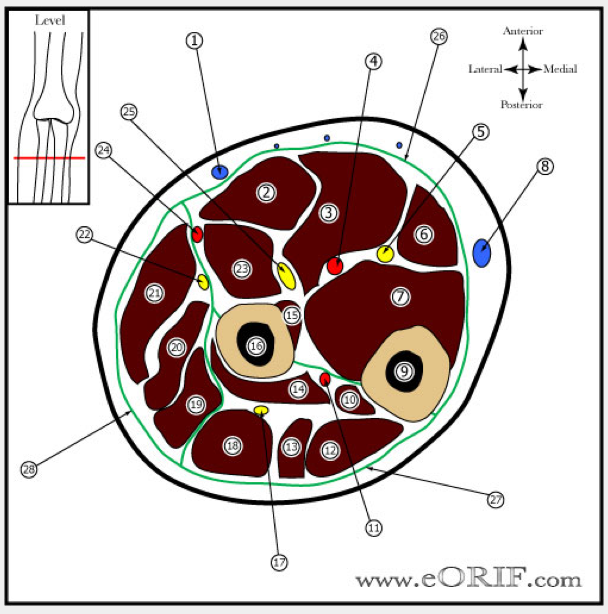

name the structures

- Cephalic vein

- FCR

- FDS

- ulnar artery

- ulnar nerve

- FCU

- FDP

- basilic vein

- ulnar shaft

- APL

- PIN

- ECU

- EDM

- Supinator

- FPL

- Radial shaft

- deep branch of radial nerve

- EDC

- ECRB

- ECRL

- BR

- Superficial radial nerve

- PT

- radial artery

- median nerve

- volar (flexors)

- Dorsal (extensors)

- mobile wad